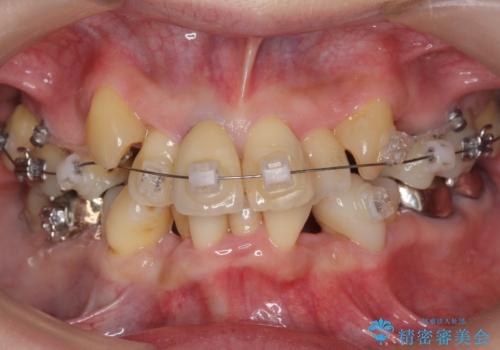

50代女性 八重歯を矯正治療 歯並びの中等度のがたつき

- ワイヤー矯正

- 八重歯の矯正を希望されて来院。

歯は入りきらないため、通常の抜歯矯正を行いました。

歯がご年齢的に動きにくいため、被せ物のやり替えを含めて治療期間の短縮を図りました。

矯正治療自体は2年半、虫歯治療等で1年ほどかかっています。

詰め物や被せ物のやり替えも併せて行っているため、治療期間を比較的短縮できました。